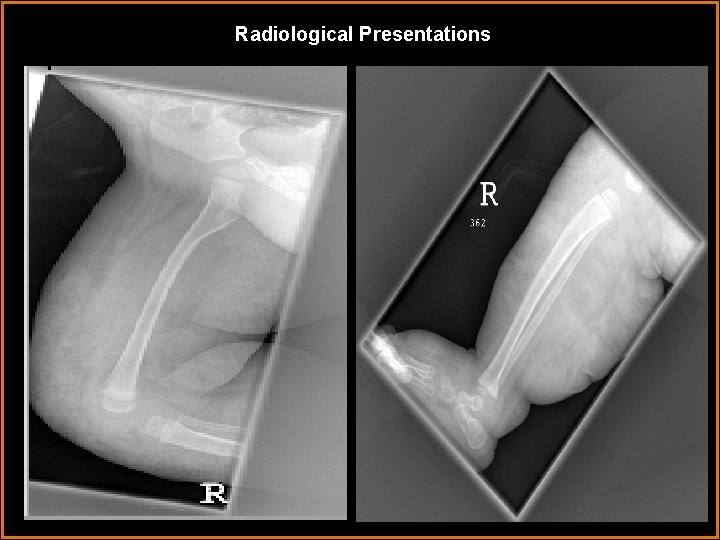

Case History 5 month infant of Pakistani descent with multiple skin lesions and asymmetric overgrowth of the right lower extremity.

Findings and Differentials Findings: The first image demonstrates prominent soft tissue overgrowth, with normal bony anatomy. The STIR coronal MRI image demonstrates prominent asymmetry between the right and left lower extremity. There is prominently increased T 2 signal in the hypertrophied subcutaneous tissues. The Axial T 1 MR sequences and the 2 D venogram demonstrates the absence of the deep venous system on the right, with prominent venous collaterals, including the large marginal vein of Servelle. Differentials: • Hemihypertrophy • Klippel-Trenaunay-Weber Syndrome • Proteus Syndrome • Kaposiform Hemangioendothelioma